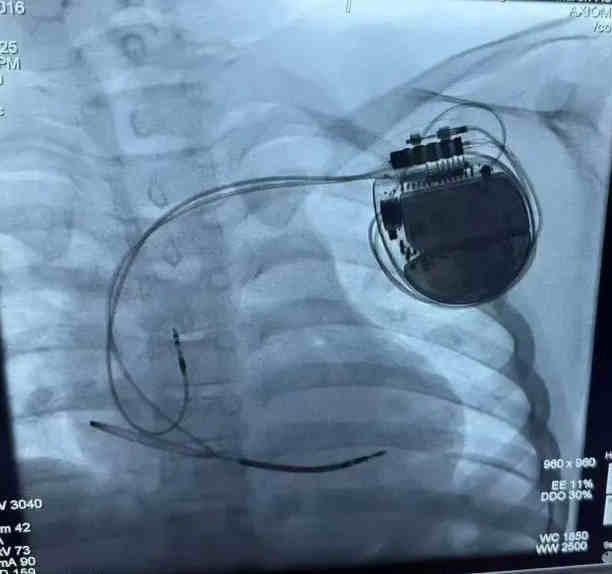

经过充分的术前准备,李磊团队为小宇实施了ICD植入术。手术在局部麻醉下进行,团队凭借精湛的技术,精准地将电极导线经静脉植入小宇的右心室,并将ICD脉冲发生器埋藏于左胸前皮下。整个手术过程顺利,耗时约1.5小时,小宇无明显不适。术后,小宇在医护人员的精心照料下恢复迅速,精神状态良好,食欲也逐渐恢复。经过一周的观察与护理,小宇顺利出院,回到了温暖的家庭怀抱。从此,他再也不用担心晕厥的困扰,可以像其他孩子一样尽情玩耍、快乐成长。